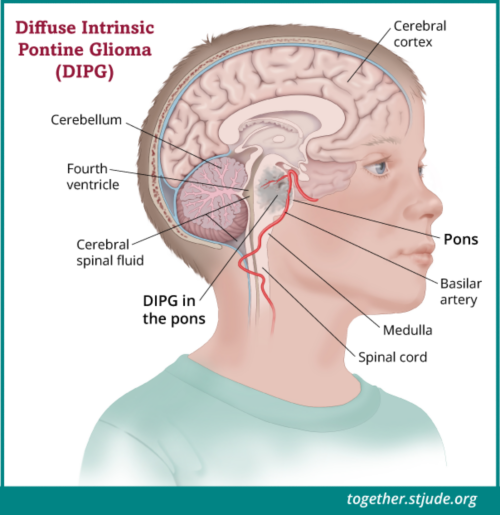

लग त र स र दर द ह सकत ह ब र न ट य मर क स क त ज न लक षण और इल ज brain tumor sign continue headache know brain tumor symptoms and treatment news nation (फाइल का प्रकार jpg)

लग त र स र दर द ह सकत ह ब र न ट य मर क स क त ज न लक षण और इल ज Brain Tumor Sign Continue Headache Know Brain Tumor Symptoms And Treatment News Nation